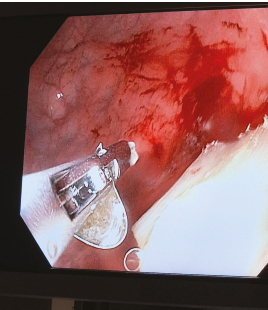

Zatímco dospělí vnímají produkty pro užívání zahřívaného tabáku jako moderní alternativu ke klasickému kouření, pro děti mohou představovat závažné zdravotní riziko. Pediatrická klinika 2. LF UK a FN Motol v uplynulém roce hospitalizovala deset dětí ve věku od osmi do patnácti měsíců, které pozřely ostrý kovový plíšek pocházející z těchto produktů.

U tří malých pacientů bylo nutné provést urgentní endoskopický zákrok, díky němuž se podařilo předejít nutnosti chirurgického výkonu.